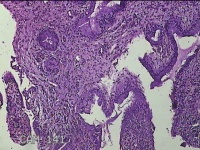

宫颈6点、10点、12点组织

性别

女

年龄

30岁

临床诊断

女性盆腔炎;宫颈炎性疾病;异常子宫出血

一般病史

宫颈HPV-56(+),TCT见非典型鳞状上皮细胞

标本名称

大体所见

1.“宫颈6点组织”:灰白暗红色不规则组织0.5x0.3x0.2cm一块。 2.“宫颈10点组织”:灰白暗红色不规则组织0.3x0.2x0.1cm一块。 3.“宫颈12点组织”:灰白暗红色不规则组织0.8x0.5x0.3cm两块。

图1

CIN1